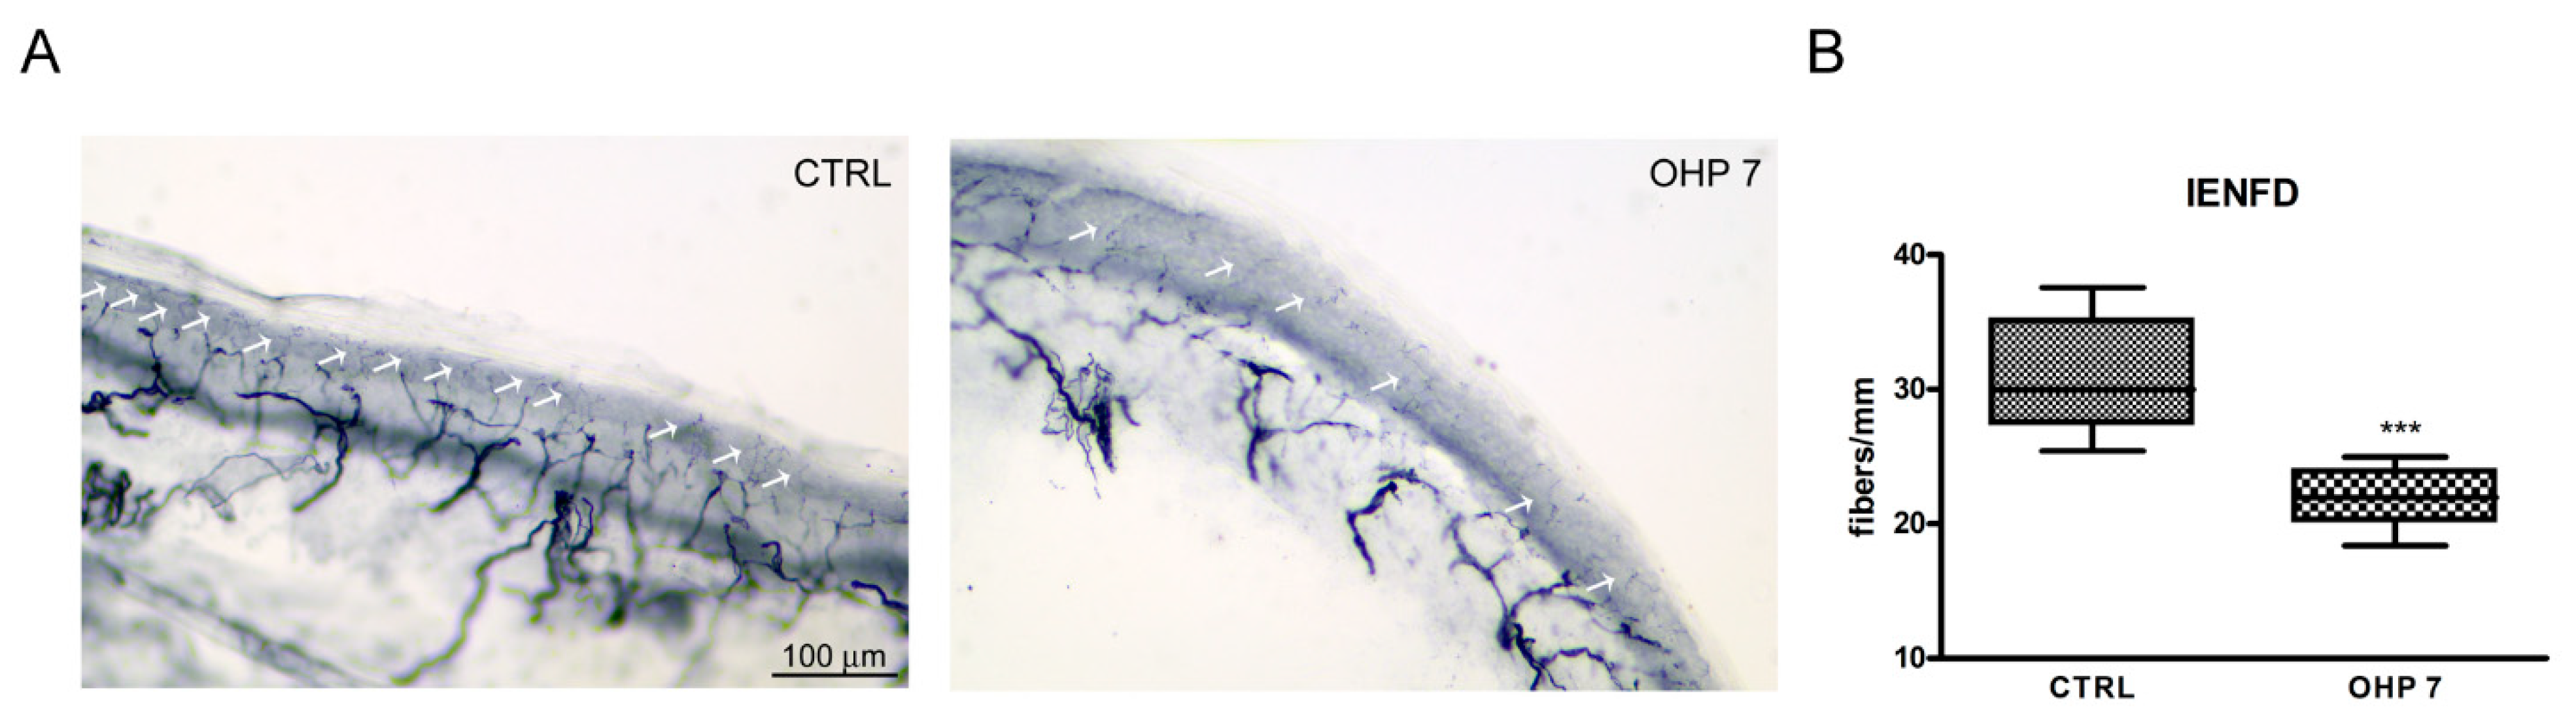

2.2.4. Intraepidermal Nerve Fiber Density (IENFD)

4.2.6. IENFD